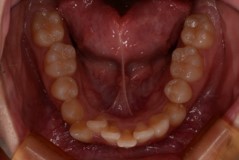

ご相談時

前歯のがたつきと口元の突出感が気になる